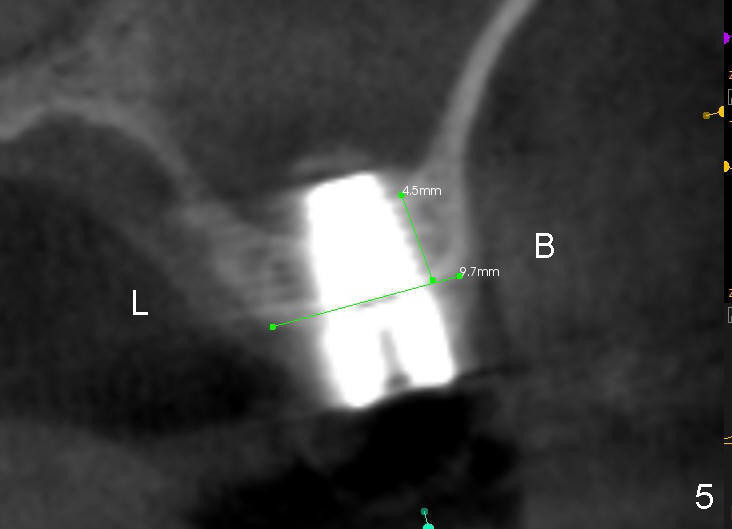

A 48-year-old lady has lost #14 for a while (Fig.1). It looks that bone density at the site of #14 is lower than that mesial to the 2nd premolar. The buccolingual width is wide clinically, although the mesiodistal distance is short (8 mm, Fig.2). A 4-mm tissue punch is used for access. When 1.5 mm pilot drill is used to start osteotomy, it feels that bone density is not low. The first bone expander (2.6 mm) cannot penetrate the bone. Therefore reamers 2.5-3.5 mm are used to increase osteotomy at the depth of 6 mm from the gingival margin. A 4.5x11 mm tap drill is inserted ~ 7 mm with resistance (Fig.3). After 5x11 mm tap, autogenous bone mixed with Osteogen is pushed into the osteotomy and upward. A 5x11 mm implant is placed with > 60 Ncm (Fig.4). After the last X-ray, the implant is torqued 5 more times so that the distal last thread may be able to be fully engaged to the bone. Fig.5 is CT coronal section at the site of #14 5 days postop (B: buccal; L: lingual). Fig.6 is taken 5 months postop with maintenance of sinus lift (*). The crown dislodges 16 months post cementation. In fact the abutment is also loose. The latter is resin bonded, followed by crown cementation (Fig.7). It appears that when the implant is 5 mm or less, the unipost should be permanently cemented in order to prevent crown displacement, particularly for a patient with bruxism and partial edentulism.